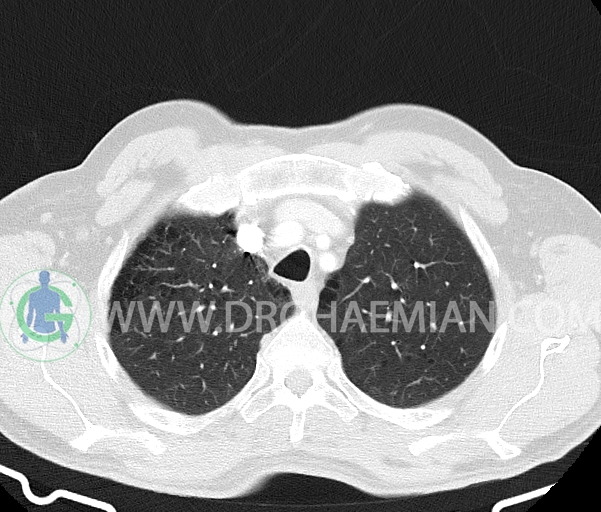

– آمفیزم سنتری لوبولار در لوب فوقانی هر دو سمت با ارجحیت در سمت راست

–آمفیزم پاراسپتال در هر دو ریه

–چند لنف نود در مدیاستن میانی و قدامی به حداکثر SAD=8mm در پره کارینا (بدون اهمیت بالینی)

–دو لنف نود در هیلوم ریه راست به حداکثر SAD=8mm